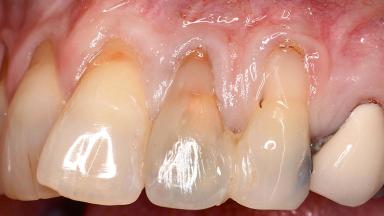

Early Implant Placement, Contour Augmentation, and Autologous Connective-Tissue Graft Using a Tunneling Technique to Replace an Upper Incisor with Generalized Gingival Recession

Variations in soft-tissue volume, evidenced either by an overabundance (Evian and coworkers 1993; Levine and McGuire1997; Dolt and Robbins 1997) or by a deficiency of soft or hard tissue can complicate implant-supported rehabilitations in the esthetic zone (Lorenzana 2008; Lorenzana and coworkers 2009). The present case illustrates the replacement of a failing upper left lateral incisor complicated by generalized severe gingival recession in the esthetic zone.

| Soft Tissue Contour and Volume | Significantly deficient |